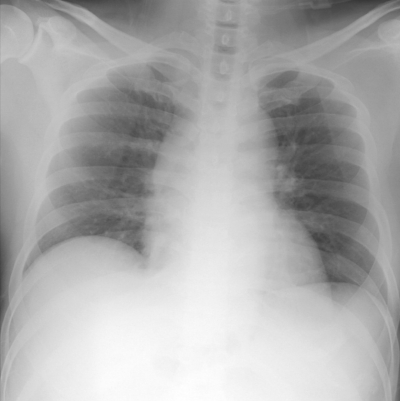

血液所見:白血球 7,700。血液生化学所見:AST 75 U/L、ALT 50 U/L、LD 361 U/L(基準 176〜353)、尿素窒素 17 mg/dL、クレアチニン 0.6 mg/dL、尿酸 6.4 mg/dL、血糖 115 mg/dL、Na 135 mEq/L、K 3.8 mEq/L、Cl 102 mEq/L、トロポニンT陰性。心電図と胸部エックス線写真とを別に示す。モニター装着や静脈路確保などの処置を行った。